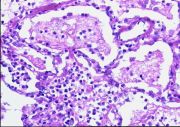

| 2021年12月10日 (五) 13:22 | 23 号切片-大叶性肺炎-镜下观3-灰色肝样变期-见纤维素穿过肺泡间孔.jpg (文件) |  |

185 KB | Cirno.9 | 基于MsUpload的文件上传 | 1 |